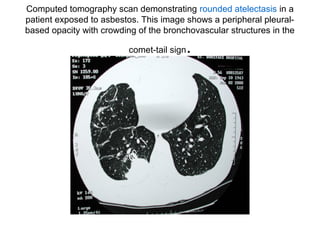

Computed tomography scan demonstrating rounded atelectasis in a

patient exposed to asbestos. This image shows a peripheral pleuralbased opacity with crowding of the bronchovascular structures in the

comet-tail sign